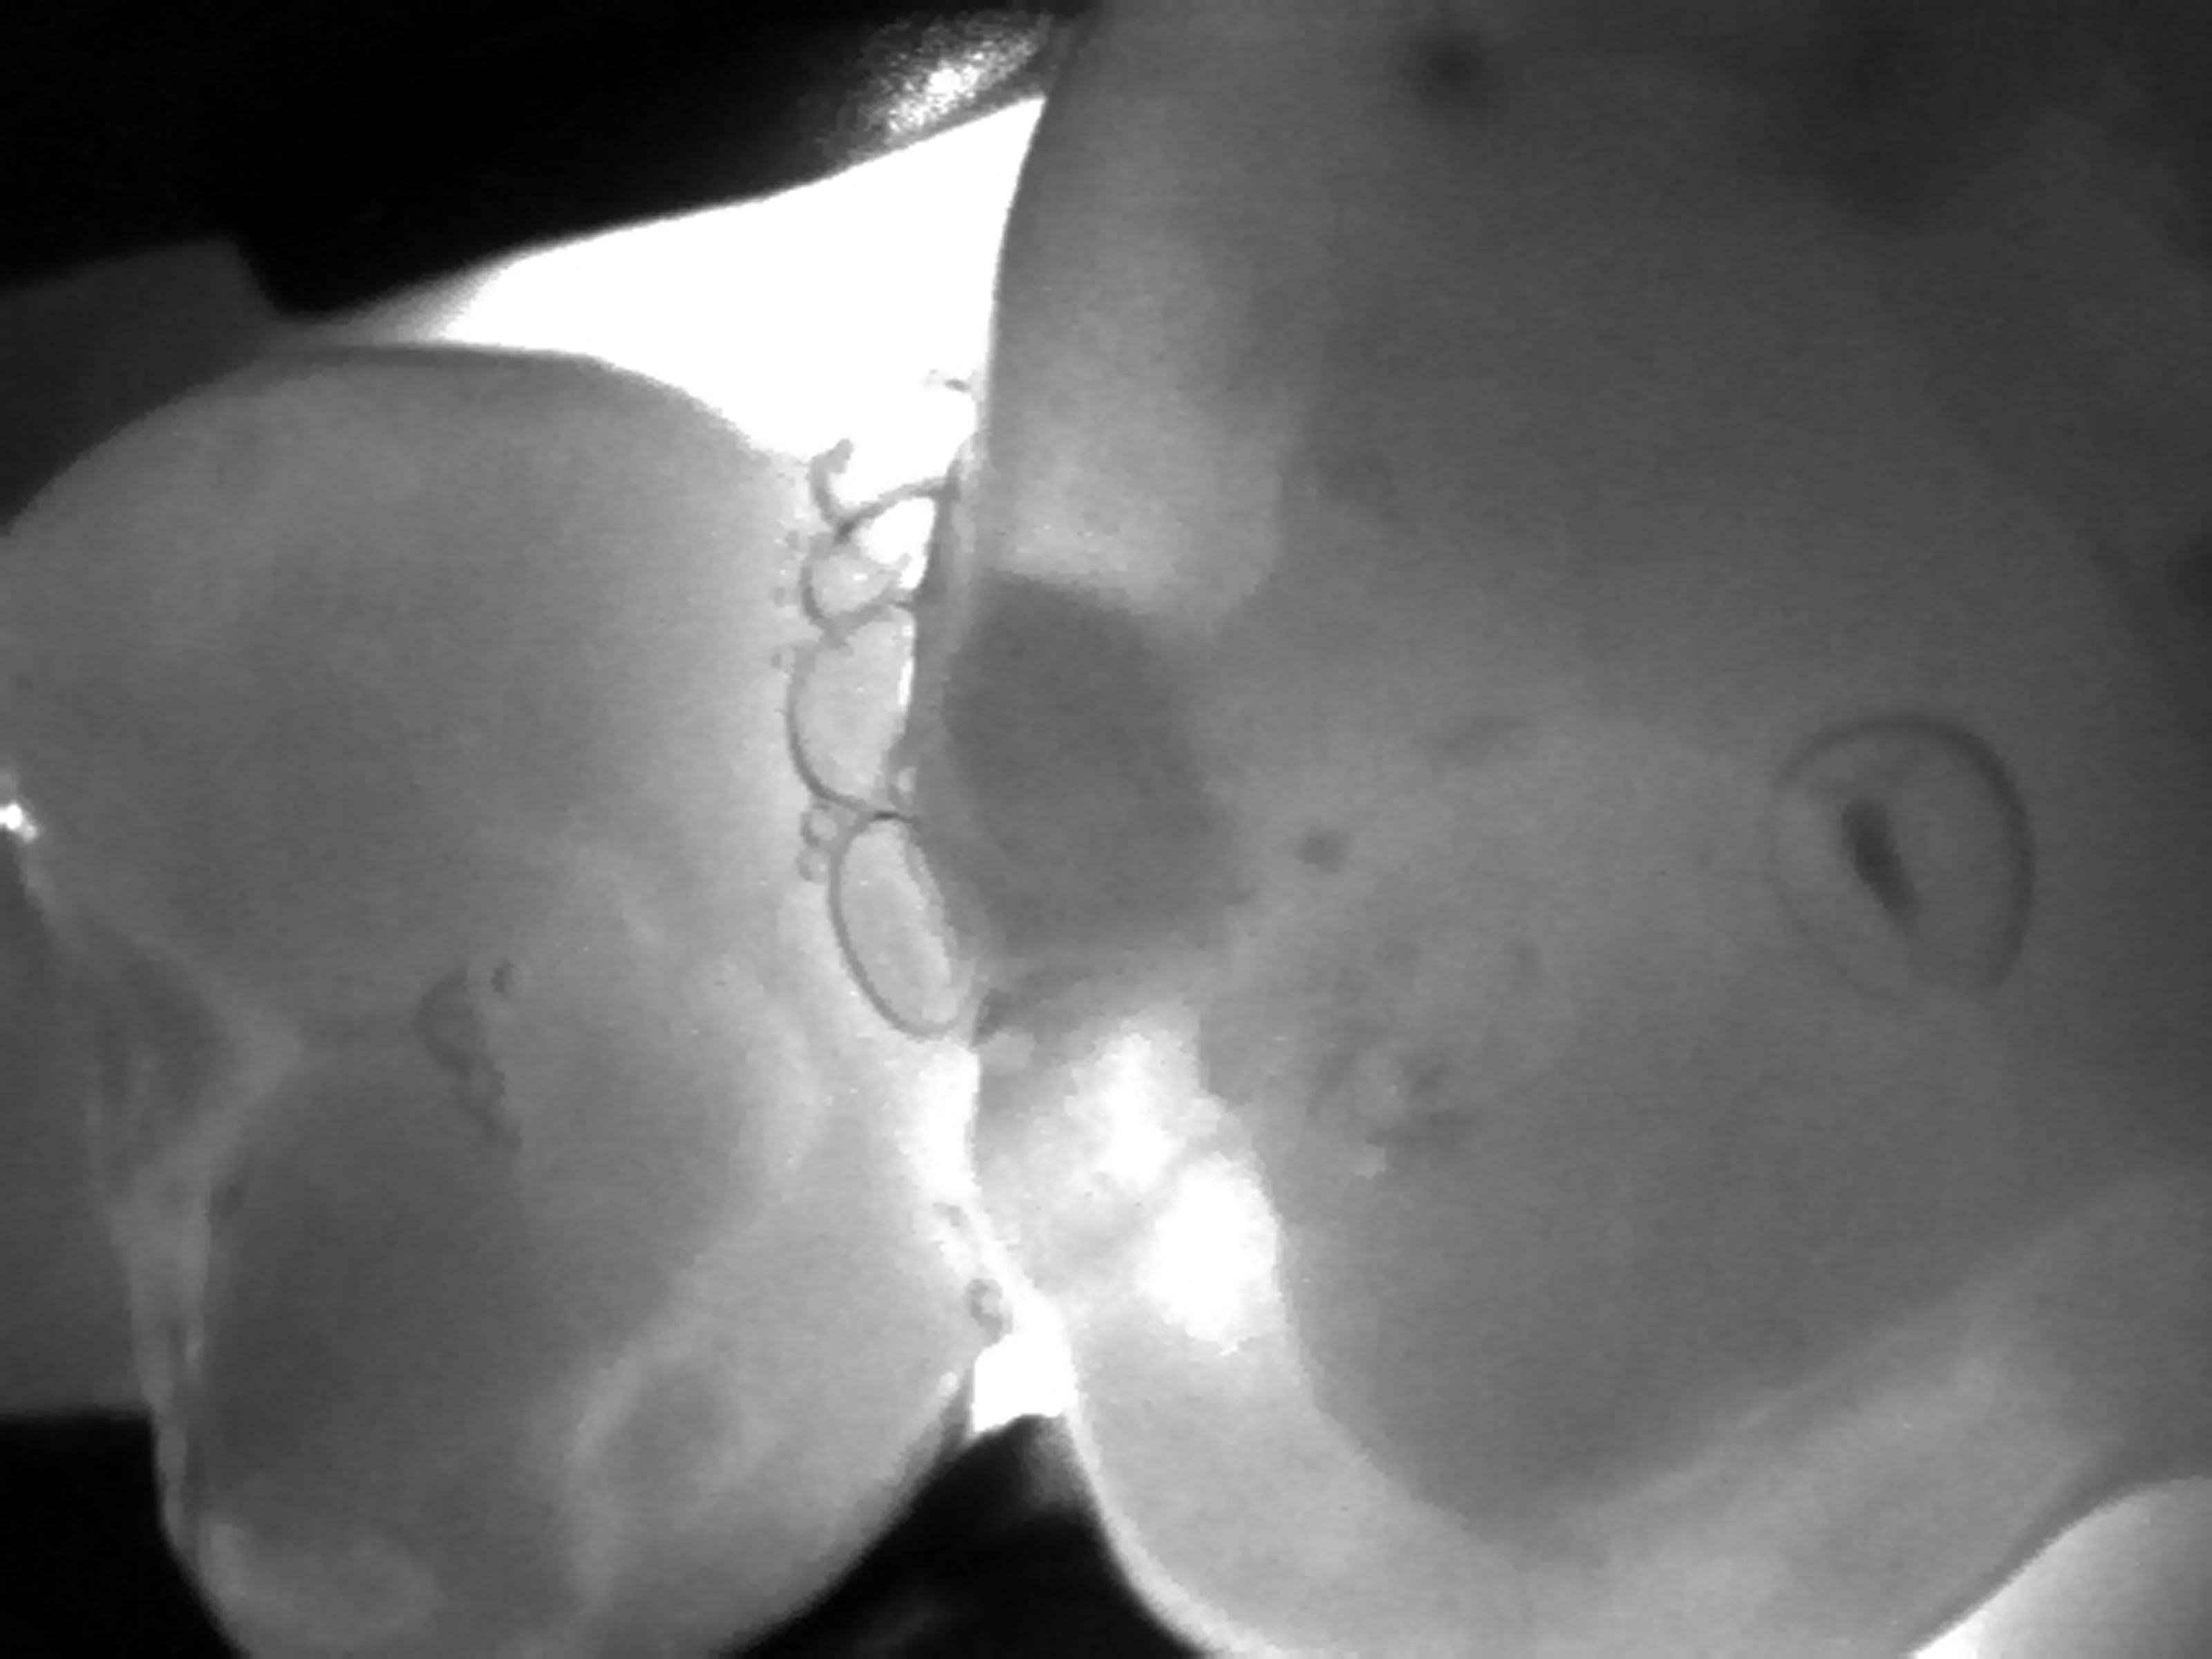

Zdjęcie lub film z badania danego zęba jest analizowane przez lekarza dentystę w poszukiwaniu wszelkich zaciemnień powierzchni, które będą wskazywać na obecność zmiany próchnicowej. Na powierzchni okluzyjnej będą to nieregularne plamy, zlokalizowane najczęściej w okolicy bruzd zębów, wykazujące penetrację próchnicy pod szkliwo. Na powierzchniach stycznych będą to ciemne miejsca w kształcie trójkątnym lub trapezowym, szerszą ścianą skierowane w stronę zewnętrznej powierzchni szkliwa, a węższą ścianą (w przypadku trapezu) lub ostrym kątem (w przypadku trójkąta) w stronę zębiny, lub wręcz stykającą się z obrysem zębiny. Im szerszy jest kontakt tej ciemnej powierzchni z obrysem zębiny tym bardziej zaawansowany jest ubytek próchnicowy na powierzchni stycznej.

Obraz prześwietlonego zęba przedtrzonowego ze zmianą próchnicową na powierzchni stycznej uzyskany w technologii NILT przy pomocy urządzenia DIAGNOcam (KaVo).